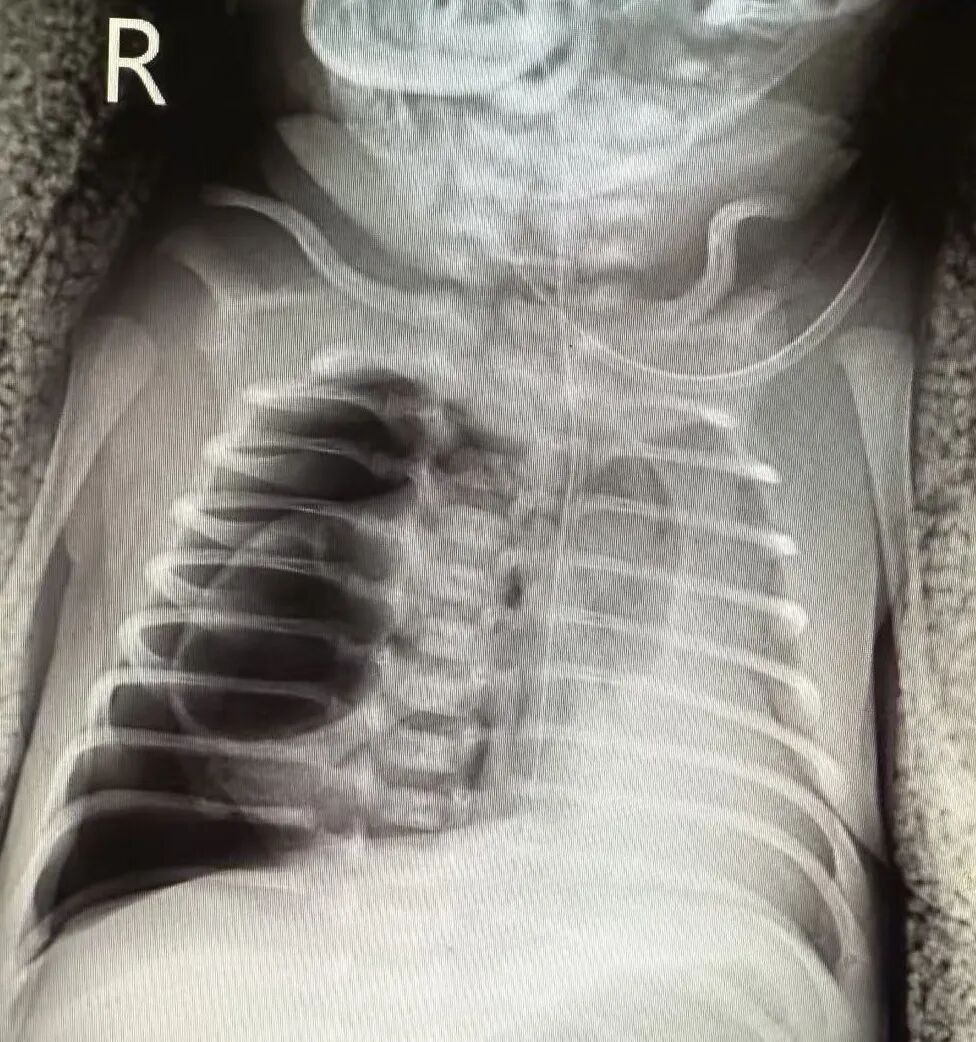

出生仅1700克的小云儿,从降临世界起就没离开过“呼吸战场”:气管插管、肺表面活性物质急救、有创呼吸机支持……命运的考验却接踵而至。生后8天,右侧胸腔突然涌出大量气胸,她再次被插上呼吸机,胸腔闭式引流管里的气泡成了父母心头不断扩大的阴影。CT片上,一个4×5厘米的囊性病灶像颗“炸弹”嵌在右肺,不仅压得右肺完全“罢工”,还把心脏和纵隔挤向左侧,连左肺的呼吸功能也岌岌可危。当地医生看着片子摇头:“这病太凶险,得找北京新生儿外科的专家!”爸爸连夜赶到首都儿童医学中心。王莹盯着片子眉头紧锁:“这是先天性肺气道畸形Ⅰ型,大疱随时可能破裂引发致命气胸,必须尽快手术!”可看着保温箱里插满管子的女儿,爸爸决定再观察几天。

然而小云儿的气胸仍在反复,“去北京!就算冒险也要试!”生后21天,父母咬牙做出决定。在当地医生护送下,载着小云儿的转运救护车一路呼啸到达了首都儿童医学中心的新生儿外科。